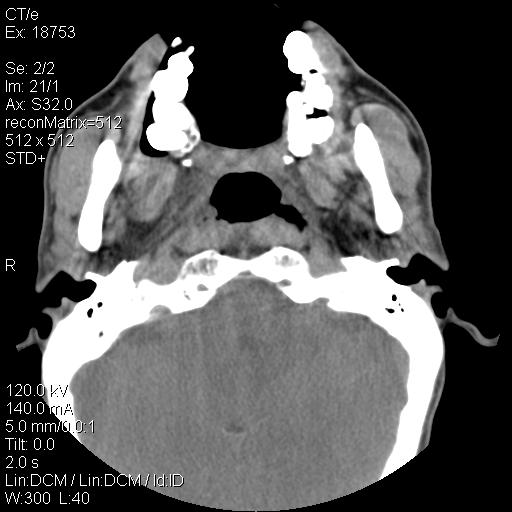

标题: CT21693:男 58岁 右侧咽部疼她2天余 PE:右侧扁桃体肿大 压痛 [打印本页]

标题: CT21693:男 58岁 右侧咽部疼她2天余 PE:右侧扁桃体肿大 压痛

右化脓性扁桃体炎症伴咽后壁脓肿形成.